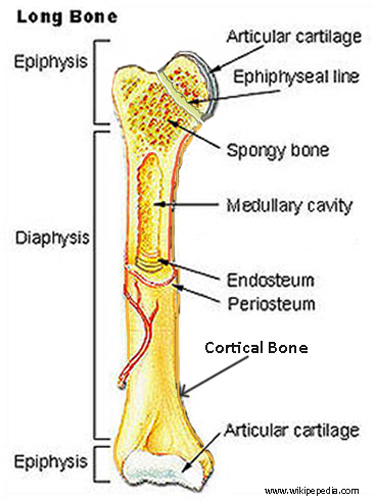

What is the physis in pediatric bones?

The cartilaginous growth plate between the diaphysis and epiphysis.

Before complete ossification, at the growth plates.

They are weaker due to immature ossification.

A transverse fracture through the growth plate with complete separation of the epiphysis.

Fracture through the growth plate and metaphysis, creating a triangular metaphyseal fragment.

A vertical fracture through the metaphysis, growth plate, and epiphysis.

A compression injury to the growth plate and its blood supply.